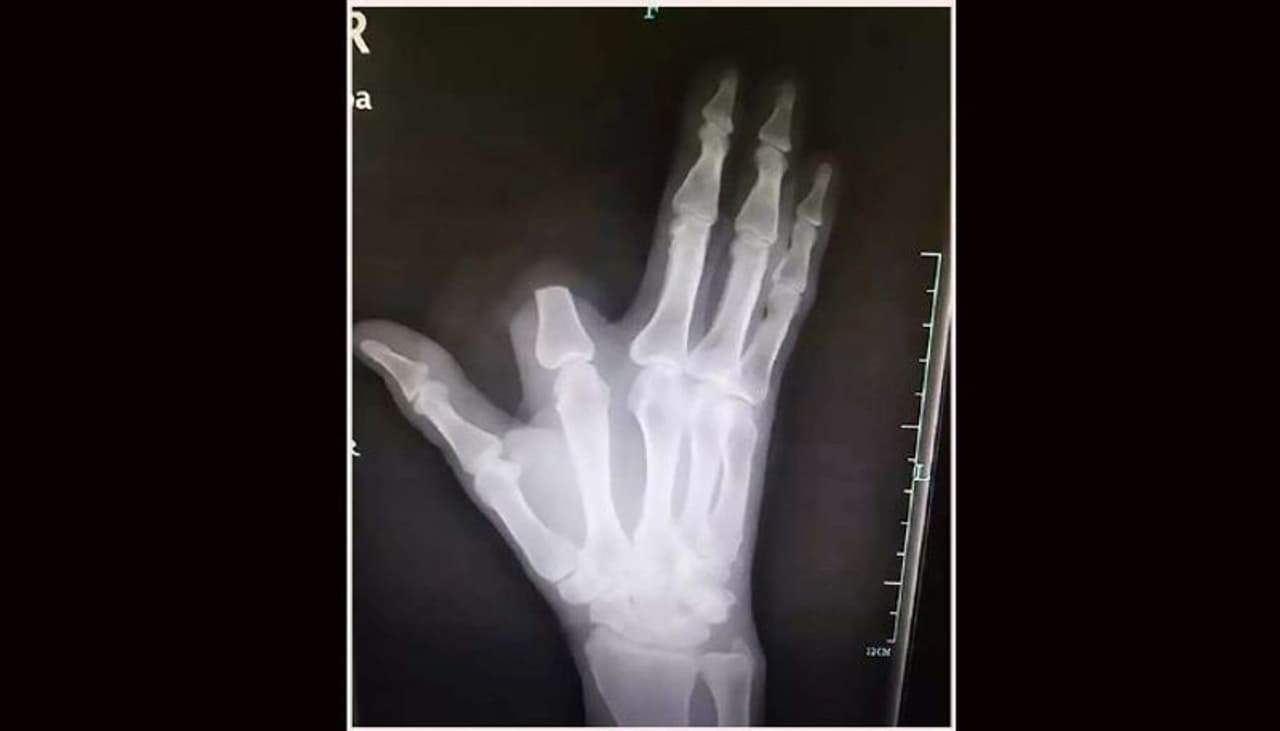

ചൂണ്ട് വിരലില് പാമ്പ് കടിയേറ്റതിനെ തുടര്ന്ന് സാഗ് വിരല് മുറിച്ചു കളയുകയായിരുന്നു. 'എന്റെ ജീവന് രക്ഷിക്കാനാണ് ഞാന് വിരല് മുറിച്ചത്. കടിച്ചത് വിഷം ചീറ്റുന്ന പാമ്പാണെന്ന് കരുതിയാണ് വിരല് മുറിച്ച് കളിഞ്ഞത്'- സാഗ് പറഞ്ഞു.

ചൈനയില് മാത്രം കാണപ്പെടുന്ന 'deinagkistrodon acutus' എന്ന ഇനം പാമ്പാണ് കടിച്ചത്. എന്നാല് ഇവ കടിച്ചാല് വിഷം ഉളളില് കയറണമെന്നില്ലെന്ന് ഗവേഷകര് പറയുന്നു. സാഗിന്റെ ഉള്ളില് വിഷം കയറിയിട്ടില്ല എന്ന് പരിശോധിച്ച ഡോക്ടര്മാര് പറഞ്ഞു. തെറ്റായ സ്വയം ചികിത്സ ചെയ്യുന്നവര്ക്ക് ഇതൊരു മുന്നറിയിപ്പ് ആണെന്നും ഡോക്ടര്മാര് പറയുന്നു.